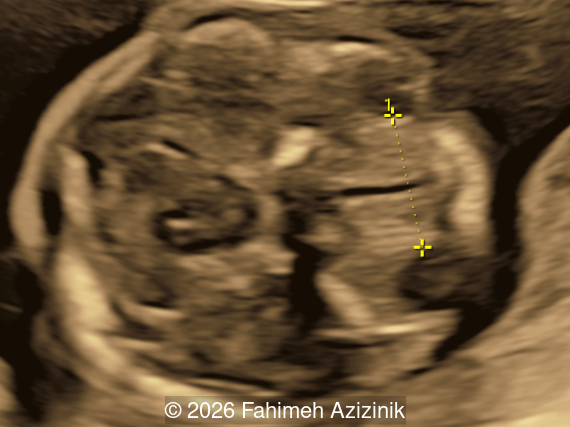

A 36-year-old pregnant woman (G2P1) was referred at 18 weeks and 4 days gestation to our tertiary center for sonographic evaluation due to the suspicion of various fetal anomalies.

Image 2

We present a case of Apert Syndrome.

Our ultrasound examination revealed the following findings:

• Bicoronal craniosynostosis

Bicoronal synostosis is the characteristic cranial hallmark of Apert syndrome, detectable sonographically from 18 weeks. Its most recognizable manifestation is turribrachycephaly, defined by an elevated cephalic index (typically >85–90%) and a tall cranial vault with marked frontal bossing [19]. On prenatal ultrasound, the face in Apert syndrome shows midface hypoplasia with a depressed nasal bridge, proptosis, hypertelorism, and frontal bossing. The extremities demonstrate syndactyly of both bone and soft tissue of the hands and feet with partial-to-complete fusion often involving second, third, and fourth digits, known as “mitten hands” and “socked feet”. In severe cases, all digits are fused, with the presence of a single nail known as “synonychia” [20]. Other ultrasound findings include mild ventriculomegaly, agenesis of the corpus callosum, deficient or absent septum pellucidum, and fusion of the cervical vertebrae at the level of C5-C6 [21]. Cardiovascular (atrial and ventricular septal defect) and genitourinary anomalies (hydronephrosis, and cryptorchidia) are present in 10% of patients [22]. Increased nuchal translucency in the first trimester [23], widely open metopic suture [24], and polyhydramnios [25] have also been reported. Three-dimensional (3D) ultrasound facilitates assessment of surface abnormalities of the face and extremities, and magnetic resonance imaging (MRI) can be used to evaluate associated intracranial conditions [26].